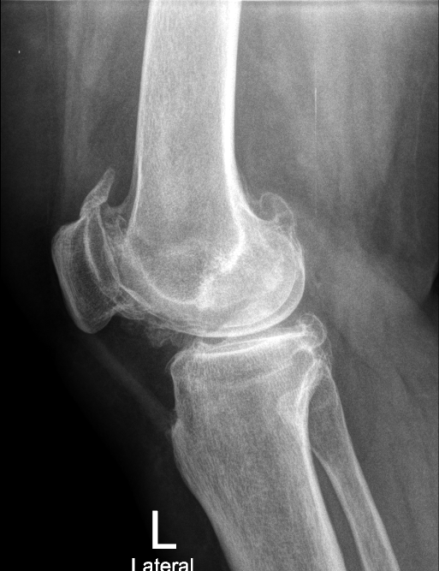

Посттравматический правосторонний гонартроз Rg III ст. Сросшийся перелом правой бедренной кости со смещением. Смешанная контрактура правого коленного сустава НФ 3 ст. Genu valgum.

После тотального цементного эндопротезирования коленного сустава эндопротезом De Puy Sigma.